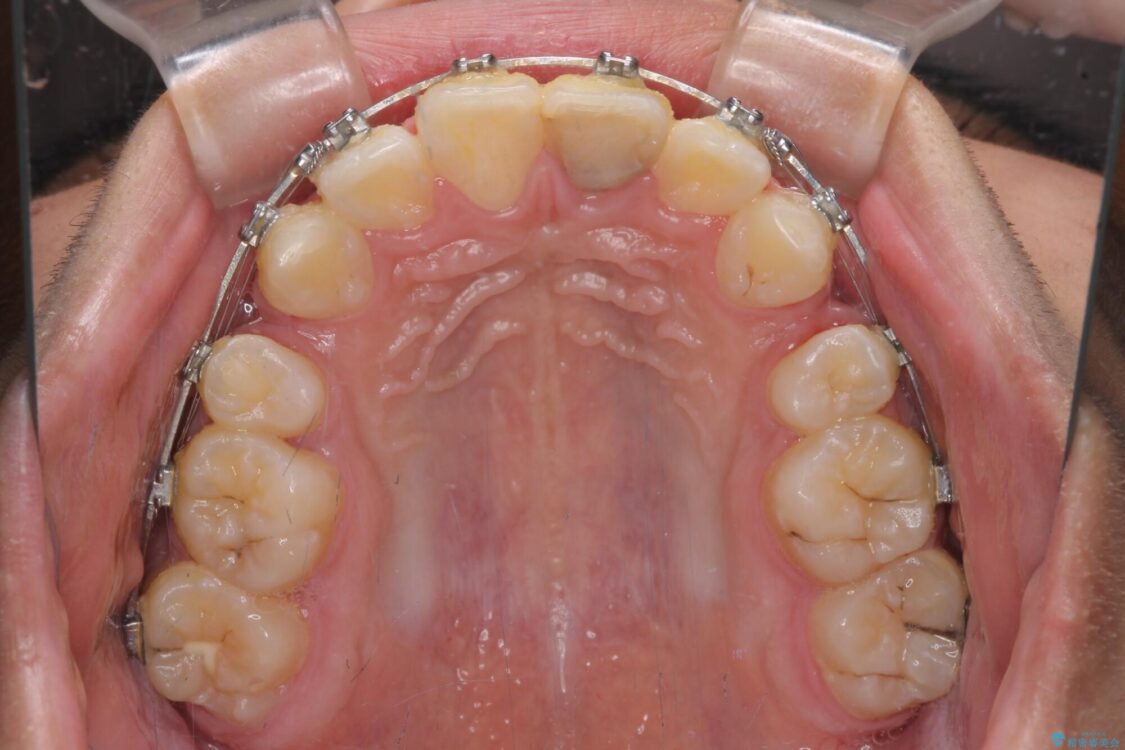

治療途中

• 膨らんだ口元 ワイヤー装置での抜歯矯正 治療途中画像

上下前歯が著しく前突している状態であったので、上下左右の第1小臼歯4本を抜歯し、ワイヤー装置にて矯正治療を行うこととしました。

舌の突出癖により、前突になったと考えられたため、舌のトレーニングをしっかりと行うよう指導しました。